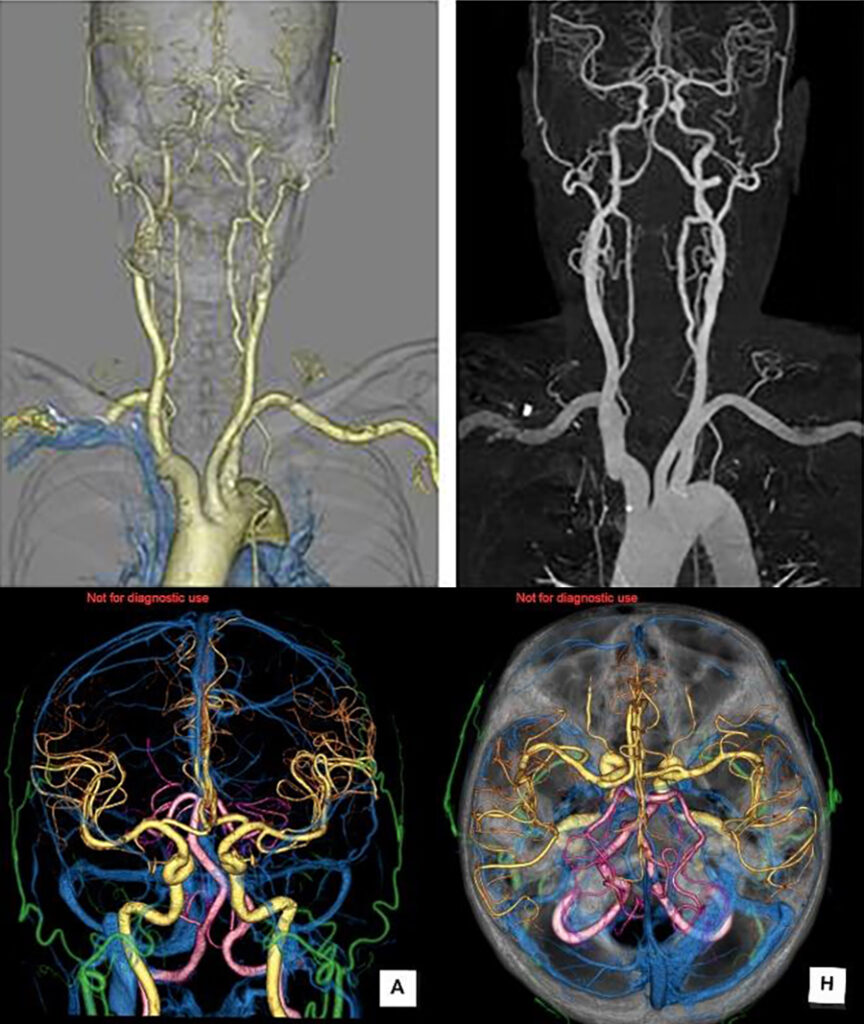

自動注入器を使用して静脈からヨード造影剤を注入し、撮影することにより血管や臓器にコントラストを付け、より詳細な情報を得る事ができます。血管精査目的の検査ではこの装置の特徴である画像ノイズ低減処理や高速撮影により造影剤の量を従来の装置より減らしながら従来の装置と変わらない画像を提供することができます。

冠動脈の石灰化や虚血性心疾患、先天性の血管走行異常など早期に発見することができます。320列CTで撮影することで、撮影時間は約1/20に、被ばく量は約1/4まで軽減できます。不整脈や息止め不良に強く、ベッドを移動させずに継ぎ目なく一度で撮影した画像なので、ミスレジストレーション(画像処理時の誤差によって生じる画像劣化)のない極めて高品質な画像を得ることになります。1心拍を最初から最後まで連続撮影することで3D画像に時間軸が加わり4D画像も作成可能となりました。